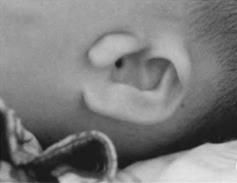

耳

外耳幾乎均有程度不一的畸形,輕者為耳前皮贅、竇道,外耳畸形可為不同程度的形態,大小、位置異常,甚至完全缺失,外耳道閉鎖。